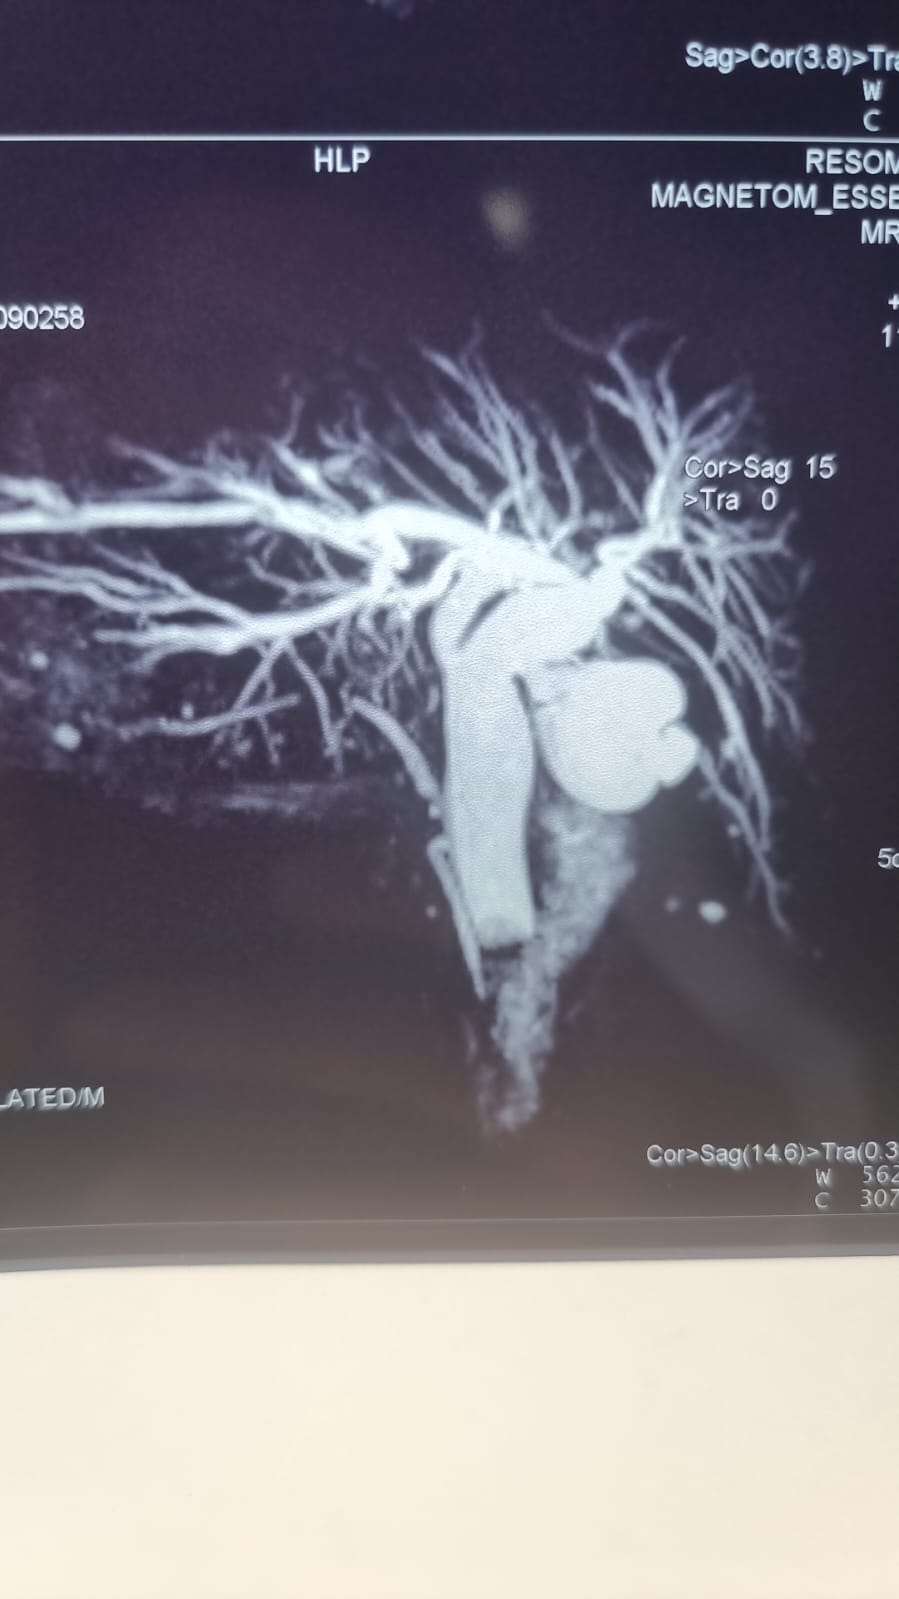

Patologías Quirúrgicas

Galería